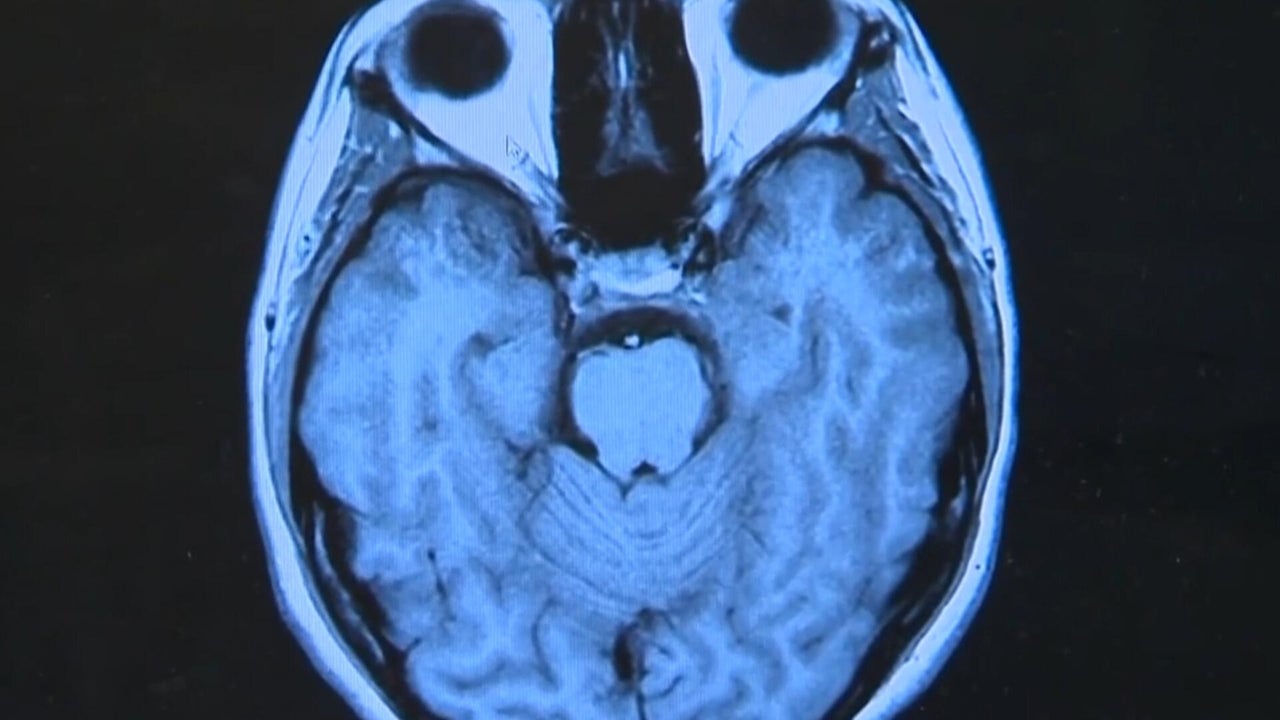

The pandemic may be over, but millions are still dealing with COVID-19's effects. The CDC estimates nearly 20 million Americans are struggling with the effects of Long COVID -- the persistence of ongoing health problems long after the infection has passed. Bradley Blackburn has more.